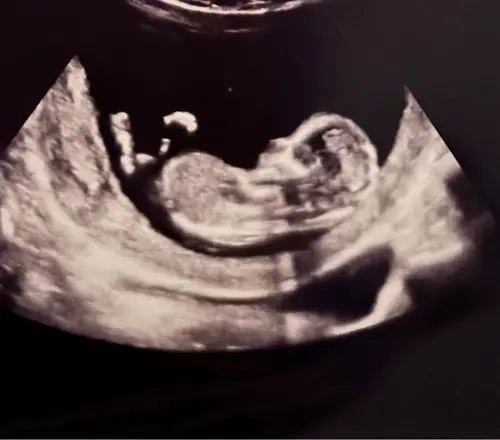

Kan iemand mij helpen bij deze? 14+2 volgende week Officele geslachtsecho maar toch erg nieuwsgierig wat jullie denken hihi:)